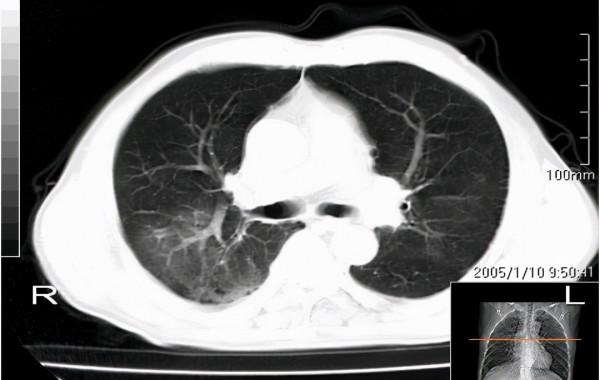

2、檢查前患者,必須拍攝X線正側位胸片,必要時做胸部CT以便確定病變的部位;